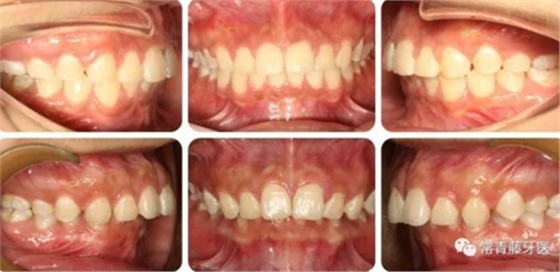

與術(shù)前對比,術(shù)后可見前牙深覆合深覆蓋得到有效改善。

上牙列得到有效內(nèi)收,上前牙凸度亦得到改善。

軟組織側(cè)貌得到明顯改善。